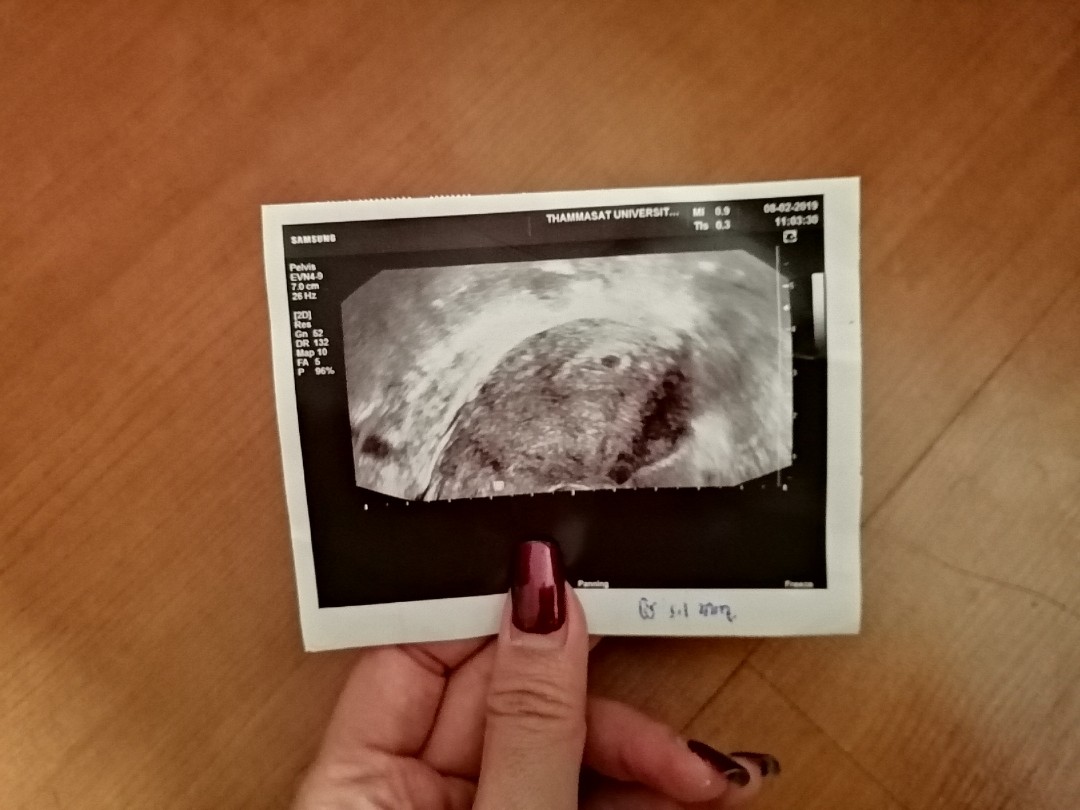

6week 1day ค่ะ

Post reply image